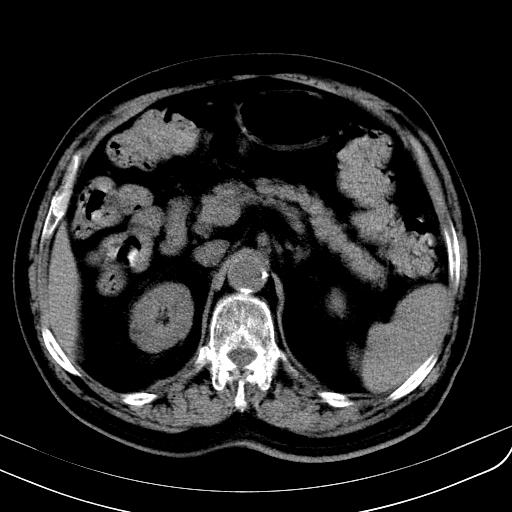

胃底靠近胃大弯处可见一圆形软组织影,直径为3.45cm,ct值约为30.1hu

边缘光滑,密度均匀,良性占位,首先考虑平滑肌瘤。

边缘光滑,密度均匀,良性占位,首先考虑平滑肌瘤。其实平滑肌瘤也是间质瘤的一种